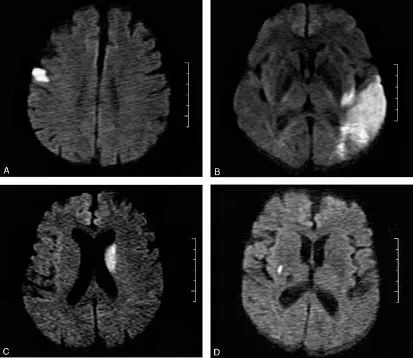

1. 本病例影像学表现提示的诊断线索:青年女性,脑内新见散在多发病灶,散在分布于多个脑动脉供血区,包括幕上幕下,皮层及深部白质,无明显占位效应,病灶周围无水肿,弥散受限,增强扫描左枕叶较大病灶不均匀强化,余病灶无明显强化。

定性诊断:本病例特点为青年女性,有明确肺癌病史,无明确神经系统症状,CT 发现颅内新发多发病灶,结合病史首先不除外转移瘤,MR 进一步检查病灶符合多发急性期脑梗死,确诊脑梗死不难,难的是确认脑梗死的发病原因。

典型影像学表现:DWI 上病灶累及 3 个或 3 个以上血管分布区,常累及前后循环,双侧多见。排除其他明确的栓塞源或与这些病变相关的其他疾病。

↑ 单发梗死:A:皮层梗死;B:皮层-皮层下梗死;C&D:皮层下梗死